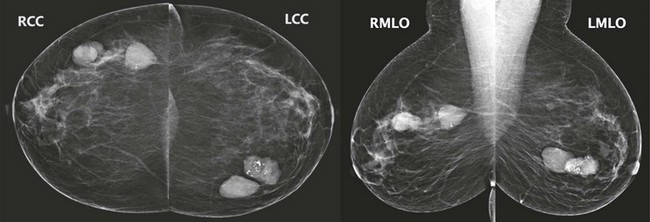

FIGURE 8-1 Multiple Bilateral Benign Masses.

Screening mammogram on a 48-year-old woman showing multiple bilateral similar-appearing masses with partially circumscribed margins. This woman had bilateral cysts previously demonstrated by US. There were no suspicious changes compared with previous mammograms. The patient was assigned BI-RADS 2, and no suspicious changes have occurred in over 2 years on subsequent mammography.